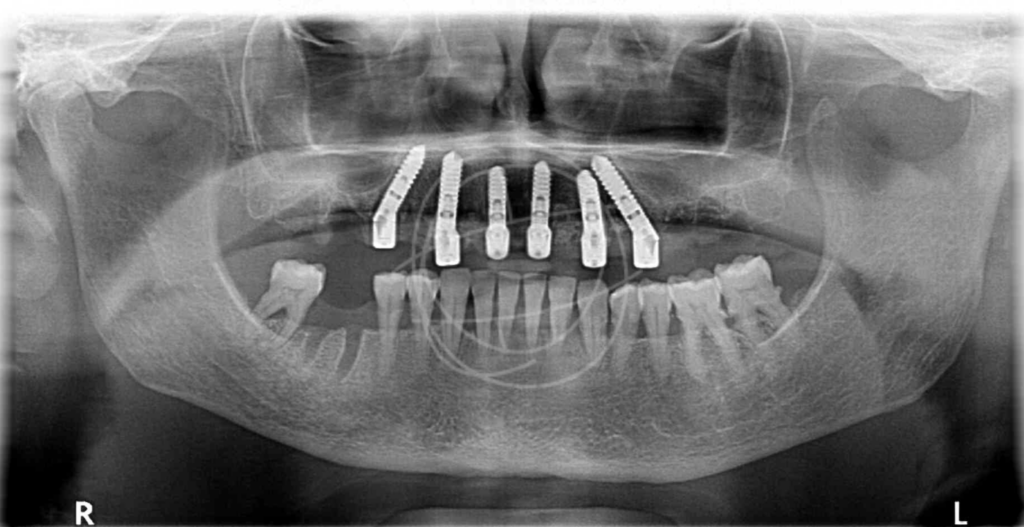

Τα οδοντικά εμφυτεύματα έχουν μεταμορφώσει τη σύγχρονη οδοντιατρική από την ανακάλυψη της οστεοενσωμάτωσης από τον Per-Ingvar Brånemark το 1952, της διαδικασίας όπου το τιτάνιο συντήκεται φυσικά με το οστό. Αυτή η ανακάλυψη οδήγησε στα πρώτα επιτυχημένα εμφυτεύματα τιτανίου το 1965, αποδεικνύοντας τη μακροπρόθεσμη σταθερότητα και ασφάλειά τους. Σήμερα, τα οστεοενσωματωμένα οδοντικά εμφυτεύματα τιτανίου αποτελούν μια αξιόπιστη, ευρέως χρησιμοποιούμενη λύση για την αποκατάσταση ελλειπουσών δοντιών και τη θεραπεία σύνθετων στοματικών παθήσεων.

Ένα οδοντικό εμφύτευμα είναι μια «τεχνητή ρίζα» από βιοσυμβατό τιτάνιο, που τοποθετείται χειρουργικά στο οστό της γνάθου. Πάνω του στηρίζεται μια στεφάνη (το «τεχνητό δόντι»), η οποία μοιάζει και λειτουργεί όπως ένα φυσικό δόντι. Γι’ αυτό και συχνά τα εμφυτεύματα θα τα ακούσετε ως «βιδωτά» ή «φυτευτά» δόντια.

Προστασία της οστικής μάζας

Επειδή αντικαθιστούν τη ρίζα του δοντιού, βοηθούν να διατηρείται το οστό «ενεργό» και μειώνουν την οστική απορρόφηση.